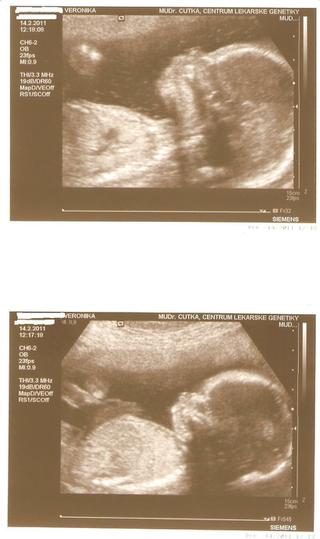

@veronikapulkertova Veru, tak to ti upřímně přeju (opočinek po zkouškách), ale i závidim :-D :-D @hhranolka ještě dotaz k těm roletám, kolik potřebujou místa ty kaslíky, aby byly schované? My budeme mít 10 cm polystyren, tak nevim, jak to vyjde u nás, jestli třeba nebudou trochu přeci jen vidět u nás se krásně frčí v tempu a klukům to jde od ruky, mam radost. Dneska tam byl vodák, tak uvidíme, jestli už pracoval nebo obhlížel. Jinak dnes jsem byla na genetickém UTZ a náš mrňous je zdravý a je to KLUK jako buk! :-D :-D

@veronikapulkertova krááááásný hotel :) ukazovala jsem manželovi :) prý, když si rozmyslím dítě, tak ještě letos pojedeme :-D ale to si asi nerozmyslím :-D tak pak dej vedet, jake to bylo a ty jsi ten strop videla nekde v akci? já o tom totiz slysim poprve :-N hold jsem amater jinak rolety opravdu doporucuju, vsichni, kteri si je dali, tak si je chvali a nemenili by ;-) @breberka zdraví je nejdulezitejsi!!! a mas dobrou fotecku,.. mimi je videt uplne ukazkove ;-) ke kastliku neporadim.. meli jsme na to uz rovnou preklady, takze my budeme mit rolety uplne schovane